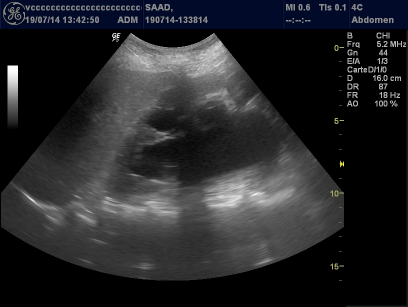

A 65year’s old diabetic women with three vaginal deliveries presented with externalized genital prolapse evolving since two years, with dysuria, painful micturition, and intermittent urinary retention. There was no urinary incontinence and the clinical examination found a genital grade IV (Baden and walker classification) prolapsed (Figure 1). Ultrasonography was performed showing bilateral ureteral dilation with thinned renal cortex especially in the right side µ and a significant post voiding residual (Figure 2). Blood creatinine was 34µmol/ml and urea at 0.89g/l. Urine culture revealed the presence of Escherichia coli, and the cervico-uterine smear was normal. Antibiotic treatment was followed by a vaginal hysterectomy with bladder placation (Figure 3). We associated a spinofixation as the Richter technique with the levator ani myorraphy. Two months later, the patient related a significant clinical improvement with disappearance of urine retention episodes and dysuria and normalization of the renal function. The ultrasonography showed a regression of hydronephrosis and good renal parenchyma.

Figure 2 Ultrasonography showing the right kidney hydronephrosis.